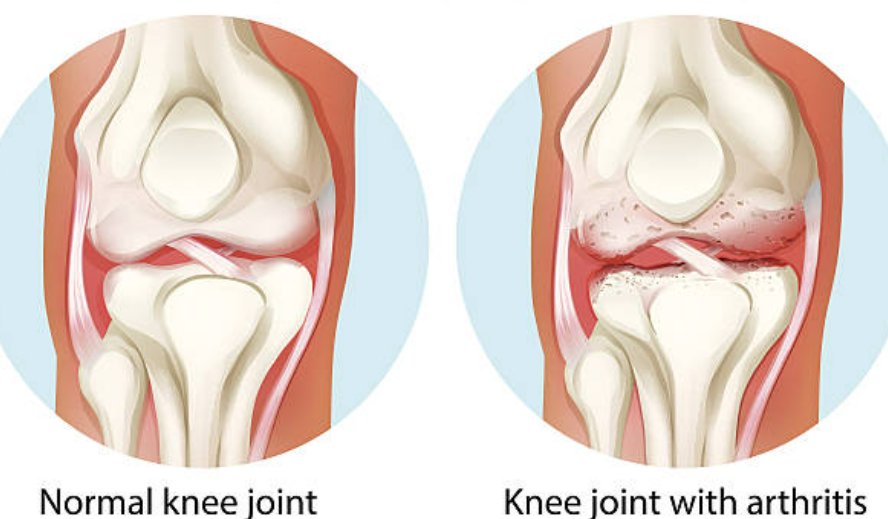

콘드로이친은 주로 상어 연골에서 추출되는 성분으로 이루어져 있습니다. 이 성분은 긴 사슬로 구성되어 있으며, 관절 내에서 연결 조직으로 작용하여 관절의 유연성과 튼튼함을 유지하는 역할을 합니다. 콘드로이친은 또한 관절 내부의 염증을 억제하고 관절염 증상을 완화하는 데 도움을 줍니다. 이러한 작용 메커니즘은 관절 건강을 향상시키고 통증을 감소시키는 데 도움이 될 수 있습니다.

1. 관절 건강 개선: 콘드로이친은 관절 내부의 연결 조직을 보강하고 관절의 유연성과 튼튼성을 증가시킴으로써 관절 건강을 개선시킬 수 있습니다.

2. 통증 완화: 콘드로이친은 관절 내부의 염증을 억제하여 통증을 완화시키는 데 도움이 될 수 있습니다.

3. 관절 기능 향상: 콘드로이친은 관절의 기능과 움직임을 개선시키는 데 도움이 될 수 있습니다.

4. 연골 보호: 콘드로이친은 연골의 손상을 예방하고 보호하는 데 도움이 될 수 있습니다.